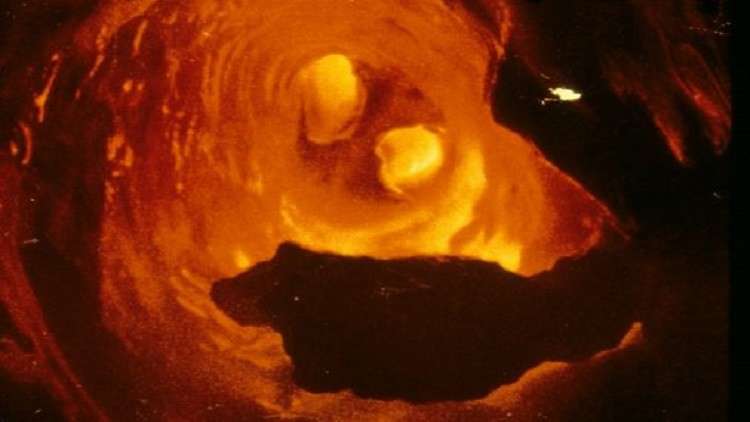

اختبار أول دواء لتنظيف الشرايين من لويحات الكوليسترول

ووفقا لإحصائيات منظمة الصحة العالمية، يعد مرض تصلب الشرايين وأمراض القلب الأخرى المرافقة أحد الأسباب الرئيسية لتطور النوبات القلبية، وبالتالي الوفيات في معظم دول العالم، حيث يبدأ هذا المرض عادة بتراكم لويحات الكوليسترول على جدران الشرايين وبعد مضي فترة يزداد سمك هذه الجدران وتفقد مرونتها.